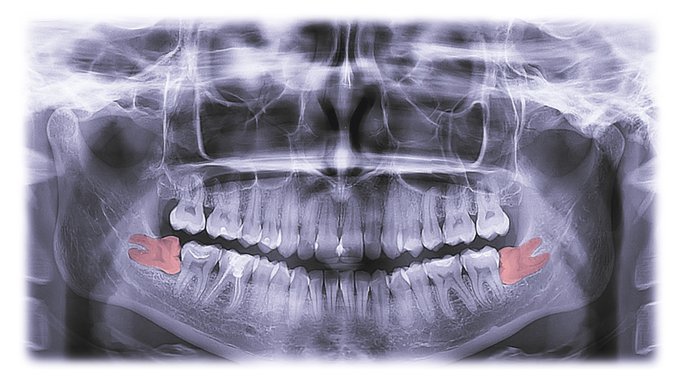

歯が大きくて顎が小さいと歯列はガタガタになり、親知らずは水平埋伏している確率が高いです。結構な確率で手前の7番の遠心根を押して吸収させるので、20才あたりが勝負です。歯科医師からは一回も知らされず、痛みが出た頃にはもう手遅れというケースがかなりあります。勉強して自己防衛しましょう。

8番に関して昔から「寝た子を起こさないように」とか言って、埋伏した状態で放置して、見て見ぬ振りをする歯科医師は多いですが、放置しても手前の7番が悪くなるだけです。患者さんはしっかりと勉強して、自分で考えて行動しましょう。

現代日本人の8番はほとんどの場合、埋まったままか、半分生える程度です。両方とも問題を起こします。埋まったままの場合は、かなりの確率で水平埋伏です。放置すると手前の7番の遠心根を押して吸収させ、7番の寿命を縮めます。特に下顎が小さい2級症例では高度の水平埋伏になっています。

親知らずのことを歯科の世界では「8番」といいます。8番をどうするかということについて、一般歯科医療ではあまり注目されていませんが、非常に重要なことです。かなり見落とされているか、見て見ぬ振りをされていることが非常に多いです。患者さんは自分で予防の知識を仕入れましょう。